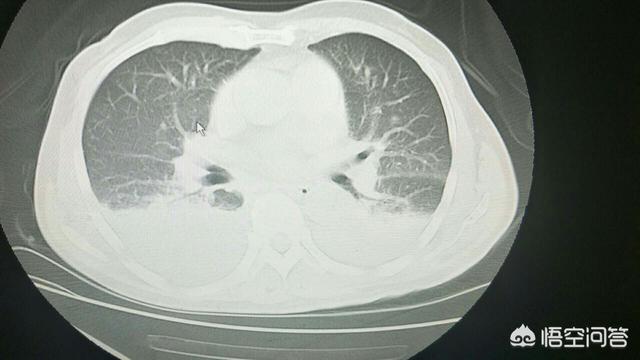

5) Système respiratoire La pneumonie chronique est fréquente.